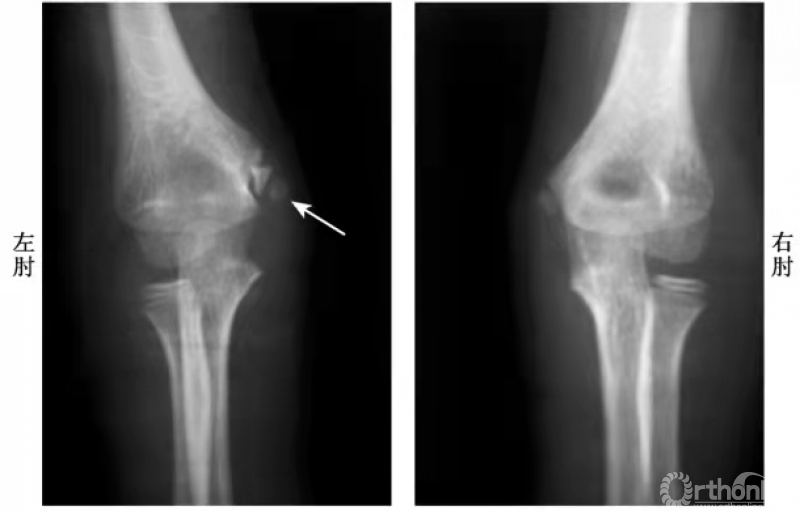

例:6岁男孩右肘伤后(图1),内上髁损伤后肿胀,局部可触到活动的骨块,但X线片未见异常(因该骨骺尚未骨化)。5年后拍片健侧(左侧)内上髁骨骺正常显现,右侧内上髁骨骺呈一三角形骨片并略下移(图2)。

图2